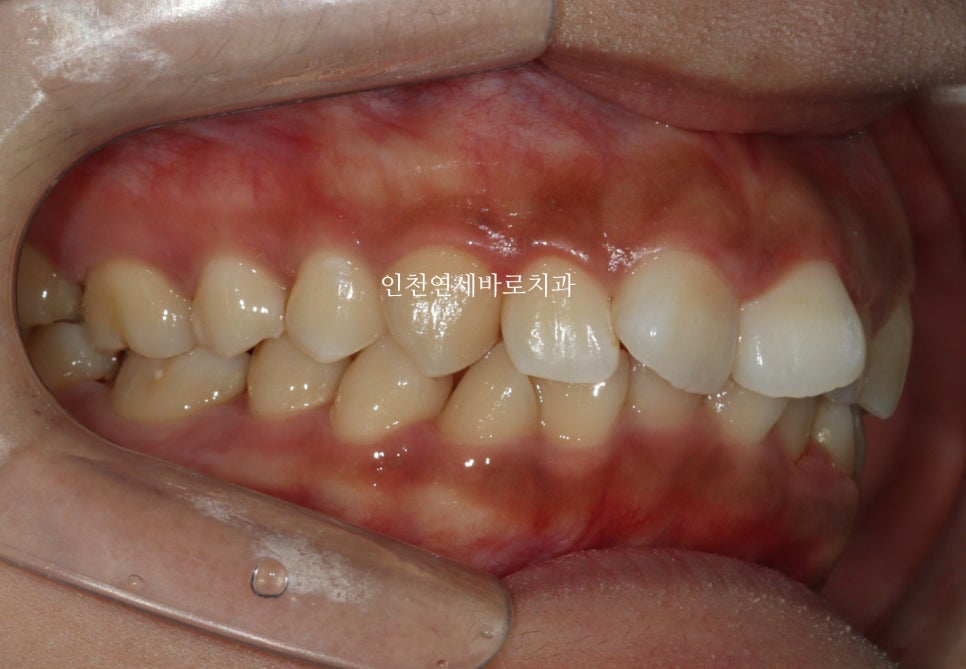

시작 후 약 4-5달 후 사진입니다.

인비절라인은 투명교정장치만 착용하는 경우가 대부분이긴합니다.

하지만 이 환자분 처럼 고무줄을 동반해야하는 경우도 있습니다.

위 사진이 7월에 재제작 했을 때 모습입니다.